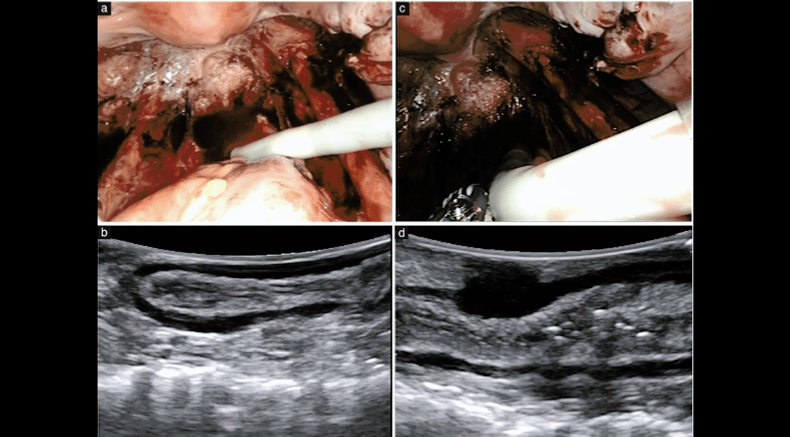

Laparoscopic views (a,c) and intraoperative ultrasound (IO-US) images (b,d) during robot-assisted laparoscopy

Nigdelis, M.P., Hudelist, G., Keckstein, J., Solomayer, E.-.-F., Daniilidis, A., Krentel, H. and Constantin, A.-.-S. (2025), Intraoperative ultrasound in minimally invasive surgery for deep endometriosis: time for new approaches. Ultrasound Obstet Gynecol, 65: 676-681. https://doi.org/10.1002/uog.29